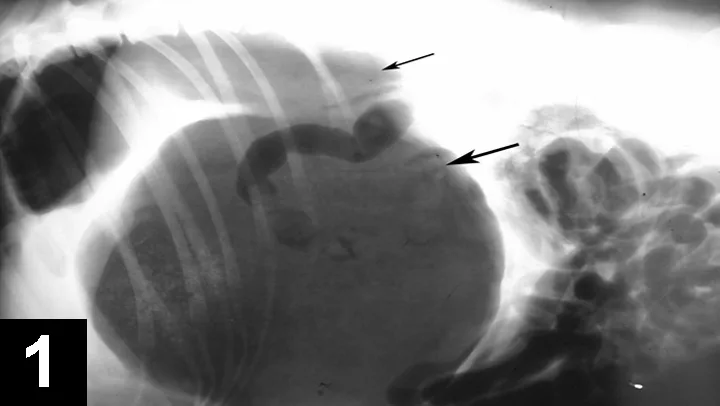

Diagnosis is based on history, clinical signs, physical examination findings, and radiography. A right lateral abdominal radiograph confirms the diagnosis but is postponed until after the patient is stabilized. GDV is confirmed when the pylorus is seen dorsally, cranially, and to the left of the midline and the fundus is ventrally displaced (Figure 1). The spleen is often large and located in a right dorsal position.

Figure 1. A right lateral recumbency abdominal radiograph demonstrates the movement of the pylorus dorsally (small arrow) and the fundus ventrally (large arrow).